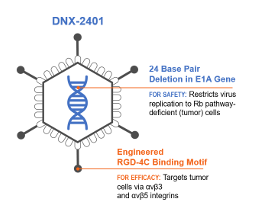

DNX-2401 is an oncolytic immunotherapy designed to fulfill the dual requirements of high potency and safety. To accomplish this, two stable genetic changes in the adenovirus genome were engineered that cause it to replicate selectively in retinoblastoma (Rb) pathway-deficient cells and infect tumor cells efficiently. Results from preclinical and clinical studies indicate that DNX-2401 (1) replicates in human tumors, (2) elicits tumor necrosis, (3) triggers intratumoral immune cell infiltration, and (4) can lead to long-term tumor destruction.

Structure of DNX-2401

Mechanism of Action of DNX-2401